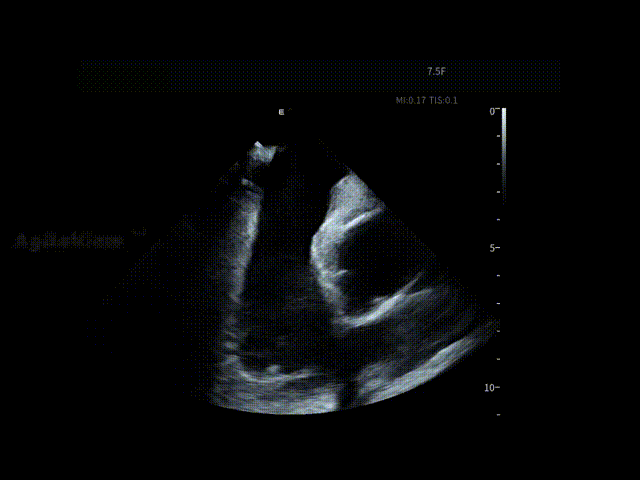

▶【高清影像护航,为手术安全保驾护航】

在消融手术开始前,邹操教授将ICE导管经股静脉穿刺进入右房进行术前筛查,为手术安全提供第一道影像保障。术者对左心房、左心耳及心包区域进行了系统性扫查,在导管消融前评估该患者不存在左房血栓情况,并进行术前心包监测。

AgileView™ ICE的高清实时超声成像使潜在风险在早期即可被发现与排除,让后续操作始终建立在“可视、可控”的安全基础之上,有效提升整体手术安全性。